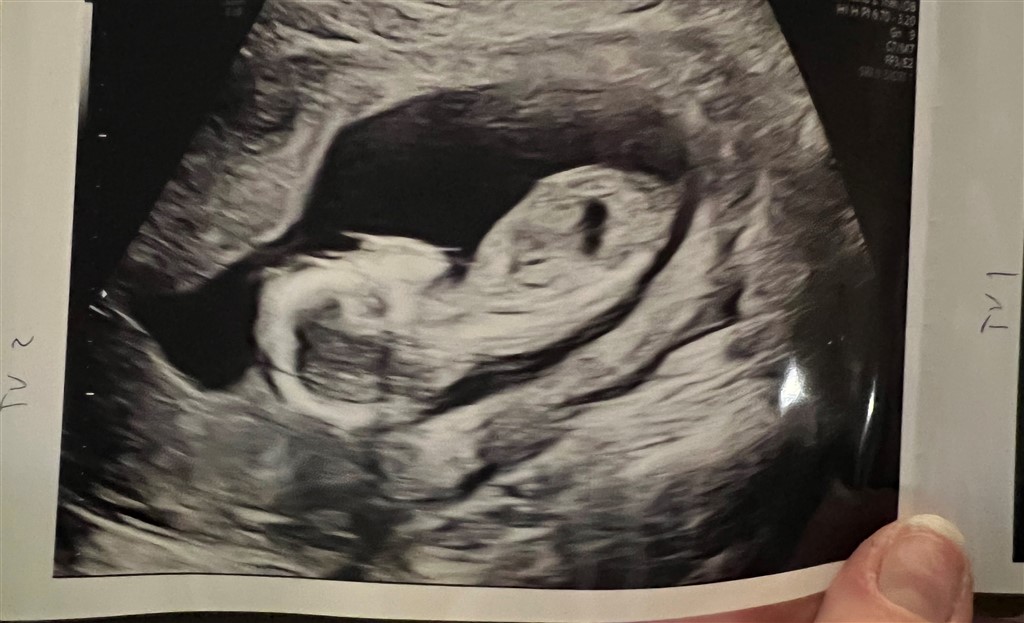

Jeg kan også kun - efter nu at have læst og set noget mere om det - se noget på billede 1. Jeg ved bare ikke, om den stikker ‘nok’ opad til, at det burde betyde, det er en dreng.

Det er jo ikke nogen eksakt videnskab, men man er jo så utroligt nysgerrig